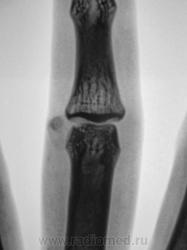

Пациент направлен на рентгенографию пальца.

Думаю это по аналогии с болезнью Кёнига - виден дефект суставной поверхности и в суставе - хондроматозное тело. Редкое наблюдение!

Вы правы, сегодня, это хондроматозное тело и вылущили.